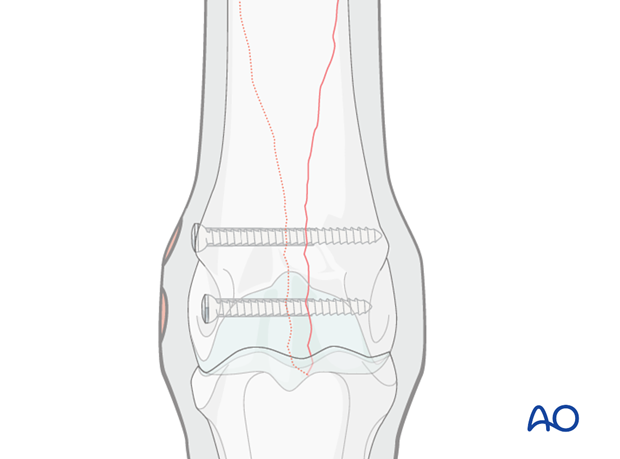

The major principles involved in lag screw fixation of these fractures are compression of the articular surface and compression across the spiraling fracture plane.

Although the glide hole is typically drilled through the smaller fragment and the thread hole across the larger fragment, this particular fracture is often repaired in the opposite manner. The major reason is that it is much safer and easier to approach the leg from the lateral side than the medial side during implant removal, which is routinely performed in the standing position. Fortunately medial condylar fractures tend to be very close to the midline so there is little difference between the width of the two fragments. The bone in this location is so strong, that 25 mm of thread engaged with a 4.5 mm cortex screw is already exceeding the strength of the screw. Although some term the lag screw technique “backward”, the strength of fixation is equally adequate.

The distal two screws across the condyle are usually placed routinely through stab incisions as described for non-displaced condylar fractures. For a detailed description see Medial incomplete condylar fractures - Lag screw fixation.